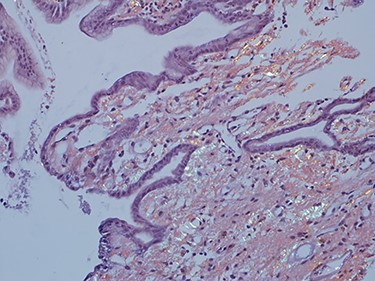

As work up for his abdominal pain and anemia he underwent gastroscopy on 29 October 2020 that revealed congested and nodular gastric mucosa (mass-like) and at lesser extend in the first and second part of duodenum (Figs 1 and 2). Biopsies were taken from the gastric lesion and duodenum. Histopathological findings from gastric mass and duodenum showed marked stromal hyalinosis, which appeared as a cellular pink material on H&E stain (Figs 3 and 5). Congo red stain (amyloid stain) showed apple green birefringence under polarized light on both gastric and duodenal biopsies (Figs 4 and 6).

High power of gastric biopsy showing prominent stromal hyalinosis, (H&E x20).